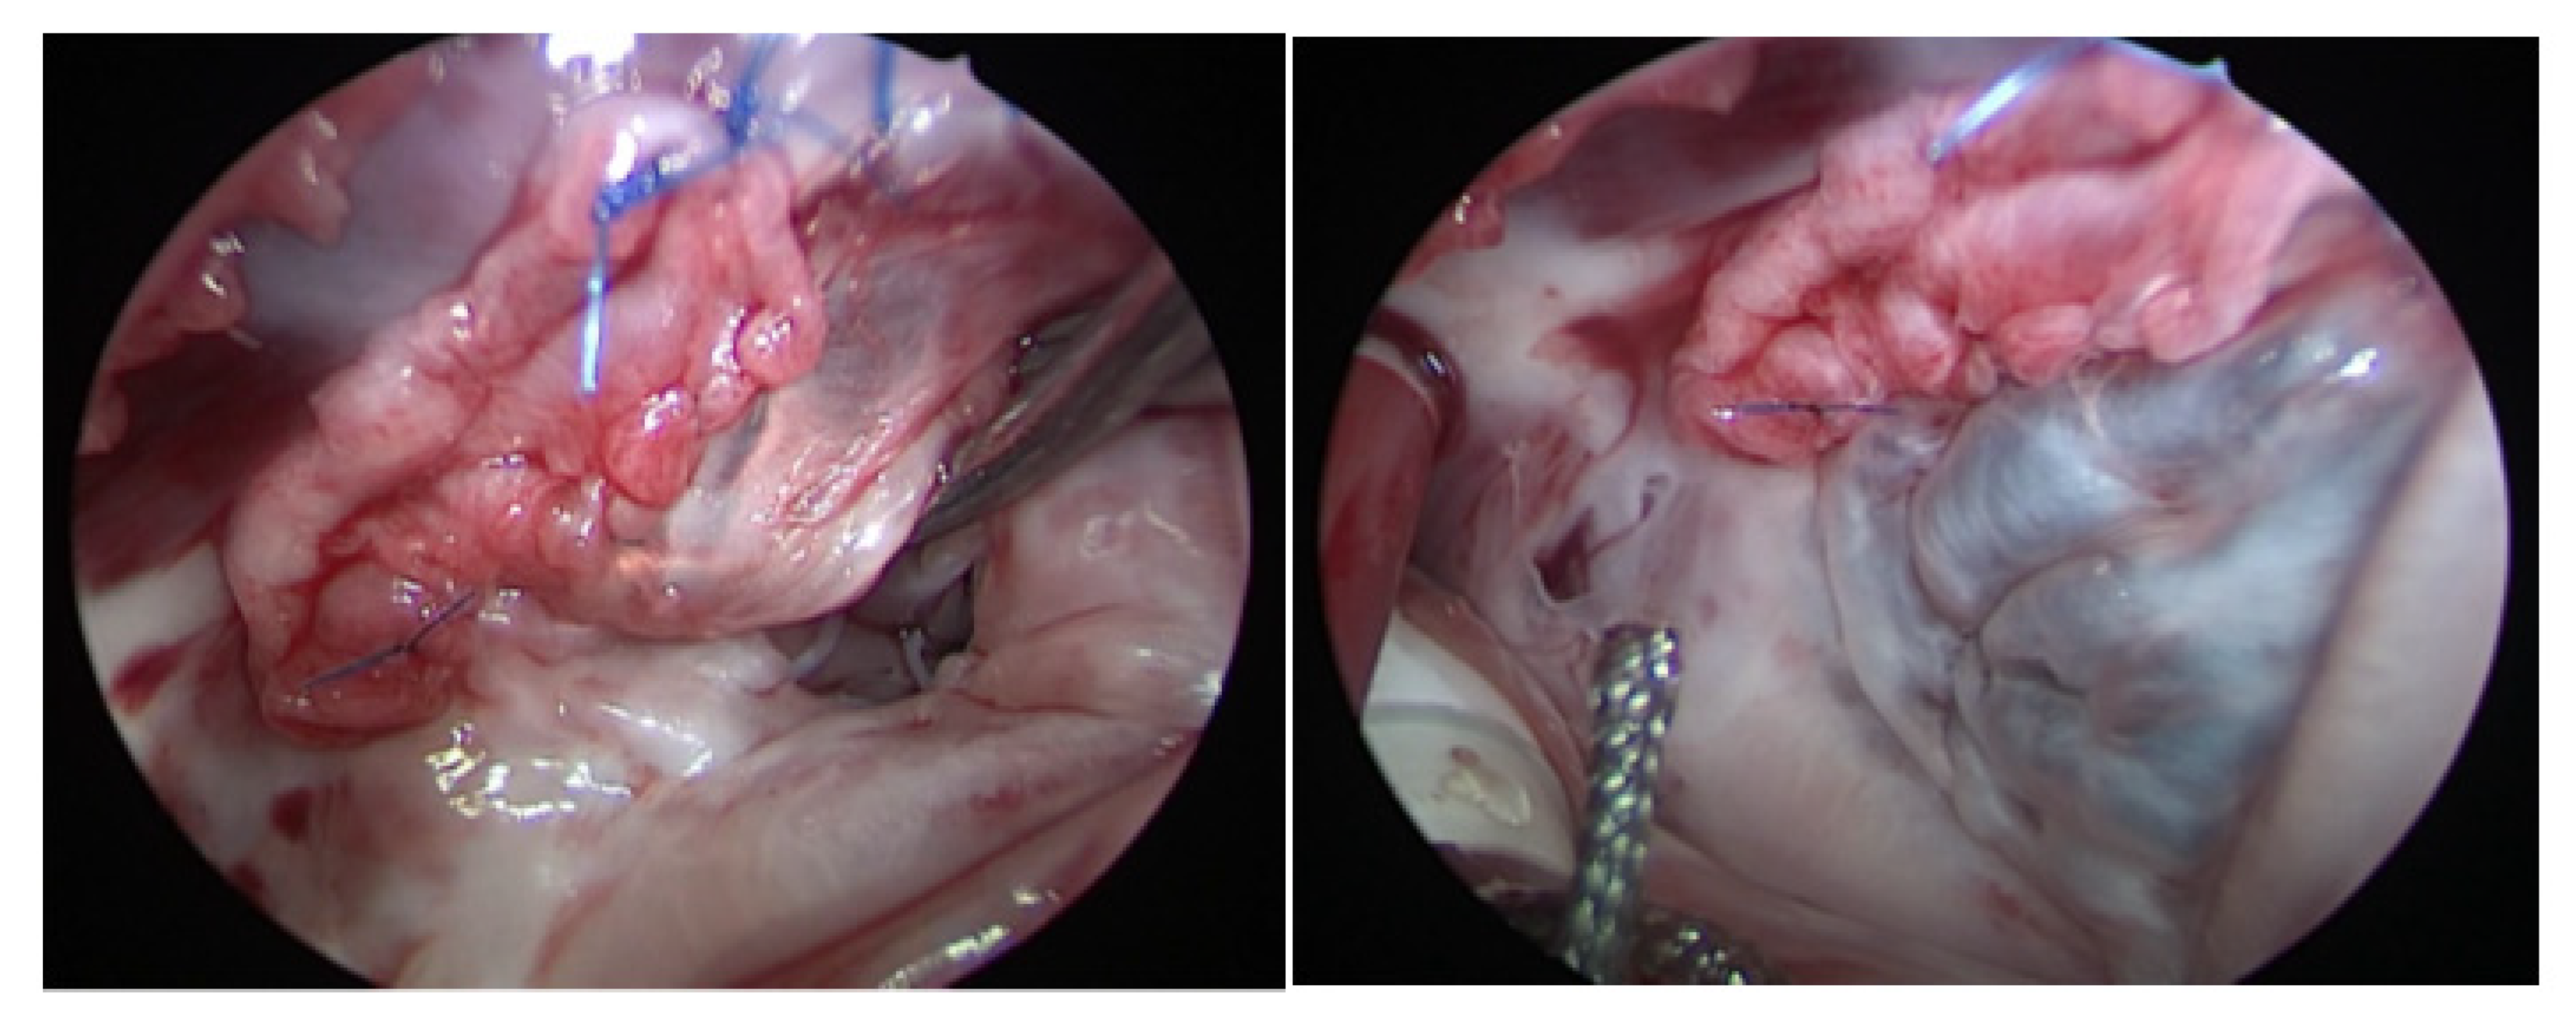

2.2. Operative Technique